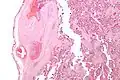

Intermediate magnification micrograph of the placental disc showing a thrombosed fetal vein, as may be seen in fetal thrombotic vasculopathy. H&E stain.

Fetal thrombotic vasculopathy is a chronic disorder characterized by thrombosis in the fetus leading to vascular obliteration and hypoperfusion.

It can be diagnosed by histomorphologic examination of the placenta and is characterized by fetal vessel thrombosis and clustered fibrotic chorionic villi without blood vessels.